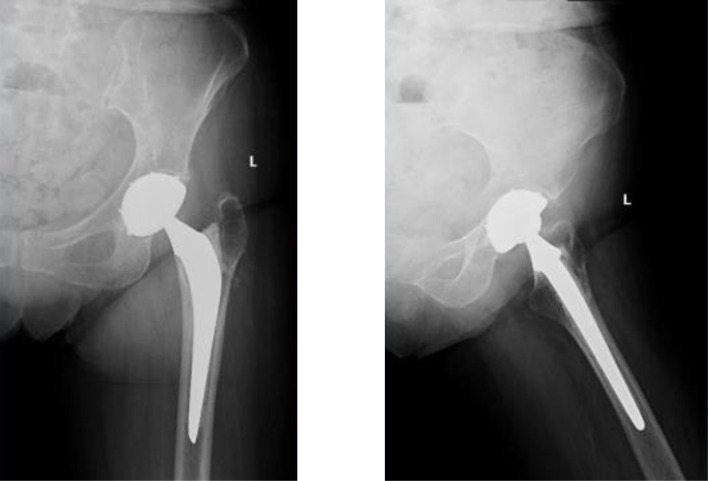

Results: The mean follow-up period was 5.96 ± 4.2 years. At the last follow-up, the mean mHHS was 92.9 ± 9.1 with 71% of the patients describing their operated hip as a forgotten hip. No dislocation or aseptic loosening events were noted. One patient developed a septic loosening of the implant. No significant radiological changes were recorded. Sixteen stems (51.6%) were placed in a neutral position, 13 (42%) in valgus (2.74 ± 1.72°), and 2 (6.4%) in varus (6.94 ± 2.02°).

Conclusion: This study emphasizes the advantage of using DMC following failed internal fixation of PFF in reducing dislocation and complication events in this high-risk population.